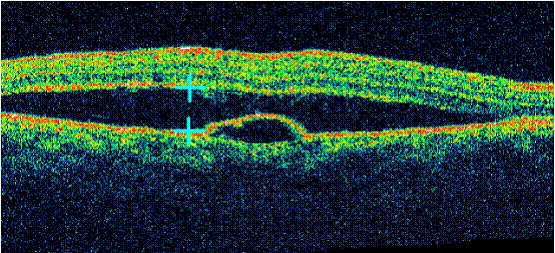

Bệnh hắc võng mạc trung tâm thanh dịch có bong biểu mô sắc tố

Bệnh võng mạc trẻ đẻ non( ROP), bệnh võng mạc đái tháo đường, hai bệnh lý gây mù lòa hàng đầu trên trẻ em và người già nhờ có OCT đã có thể chẩn đoán được hình thái, nguyên nhân, lên phương án điều trị. Hàng chục năm trước rất nhiều tổn thương đã không được đánh giá đầy đủ vì các bác sĩ chỉ có trong tay phương pháp chụp mạch hùynh quang. Đối với bệnh hắc võng mạc trung tâm thanh dịch, OCT có thể cho thấy được dịch tích tụ giữa lớp thần kinh cảm thụ và lớp biểu mô sắc tố của võng mạc, đo được kích thước của khối dịch. Ngoài ra, còn có thể xác định vị trí của điểm dò qua vị trí tổn hại hoặc bong lớp biểu mô sắc tố. Trong bệnh lỗ hoàng điểm, OCT xác định có lỗ hoàng điểm, đo được kích thước của lỗ hoàng điểm, có thể thấy được co kéo dịch kính võng mạc gây ra lỗ hoàng điểm và chiều dày võng mạc vùng xung quanh lỗ hoàng điểm...